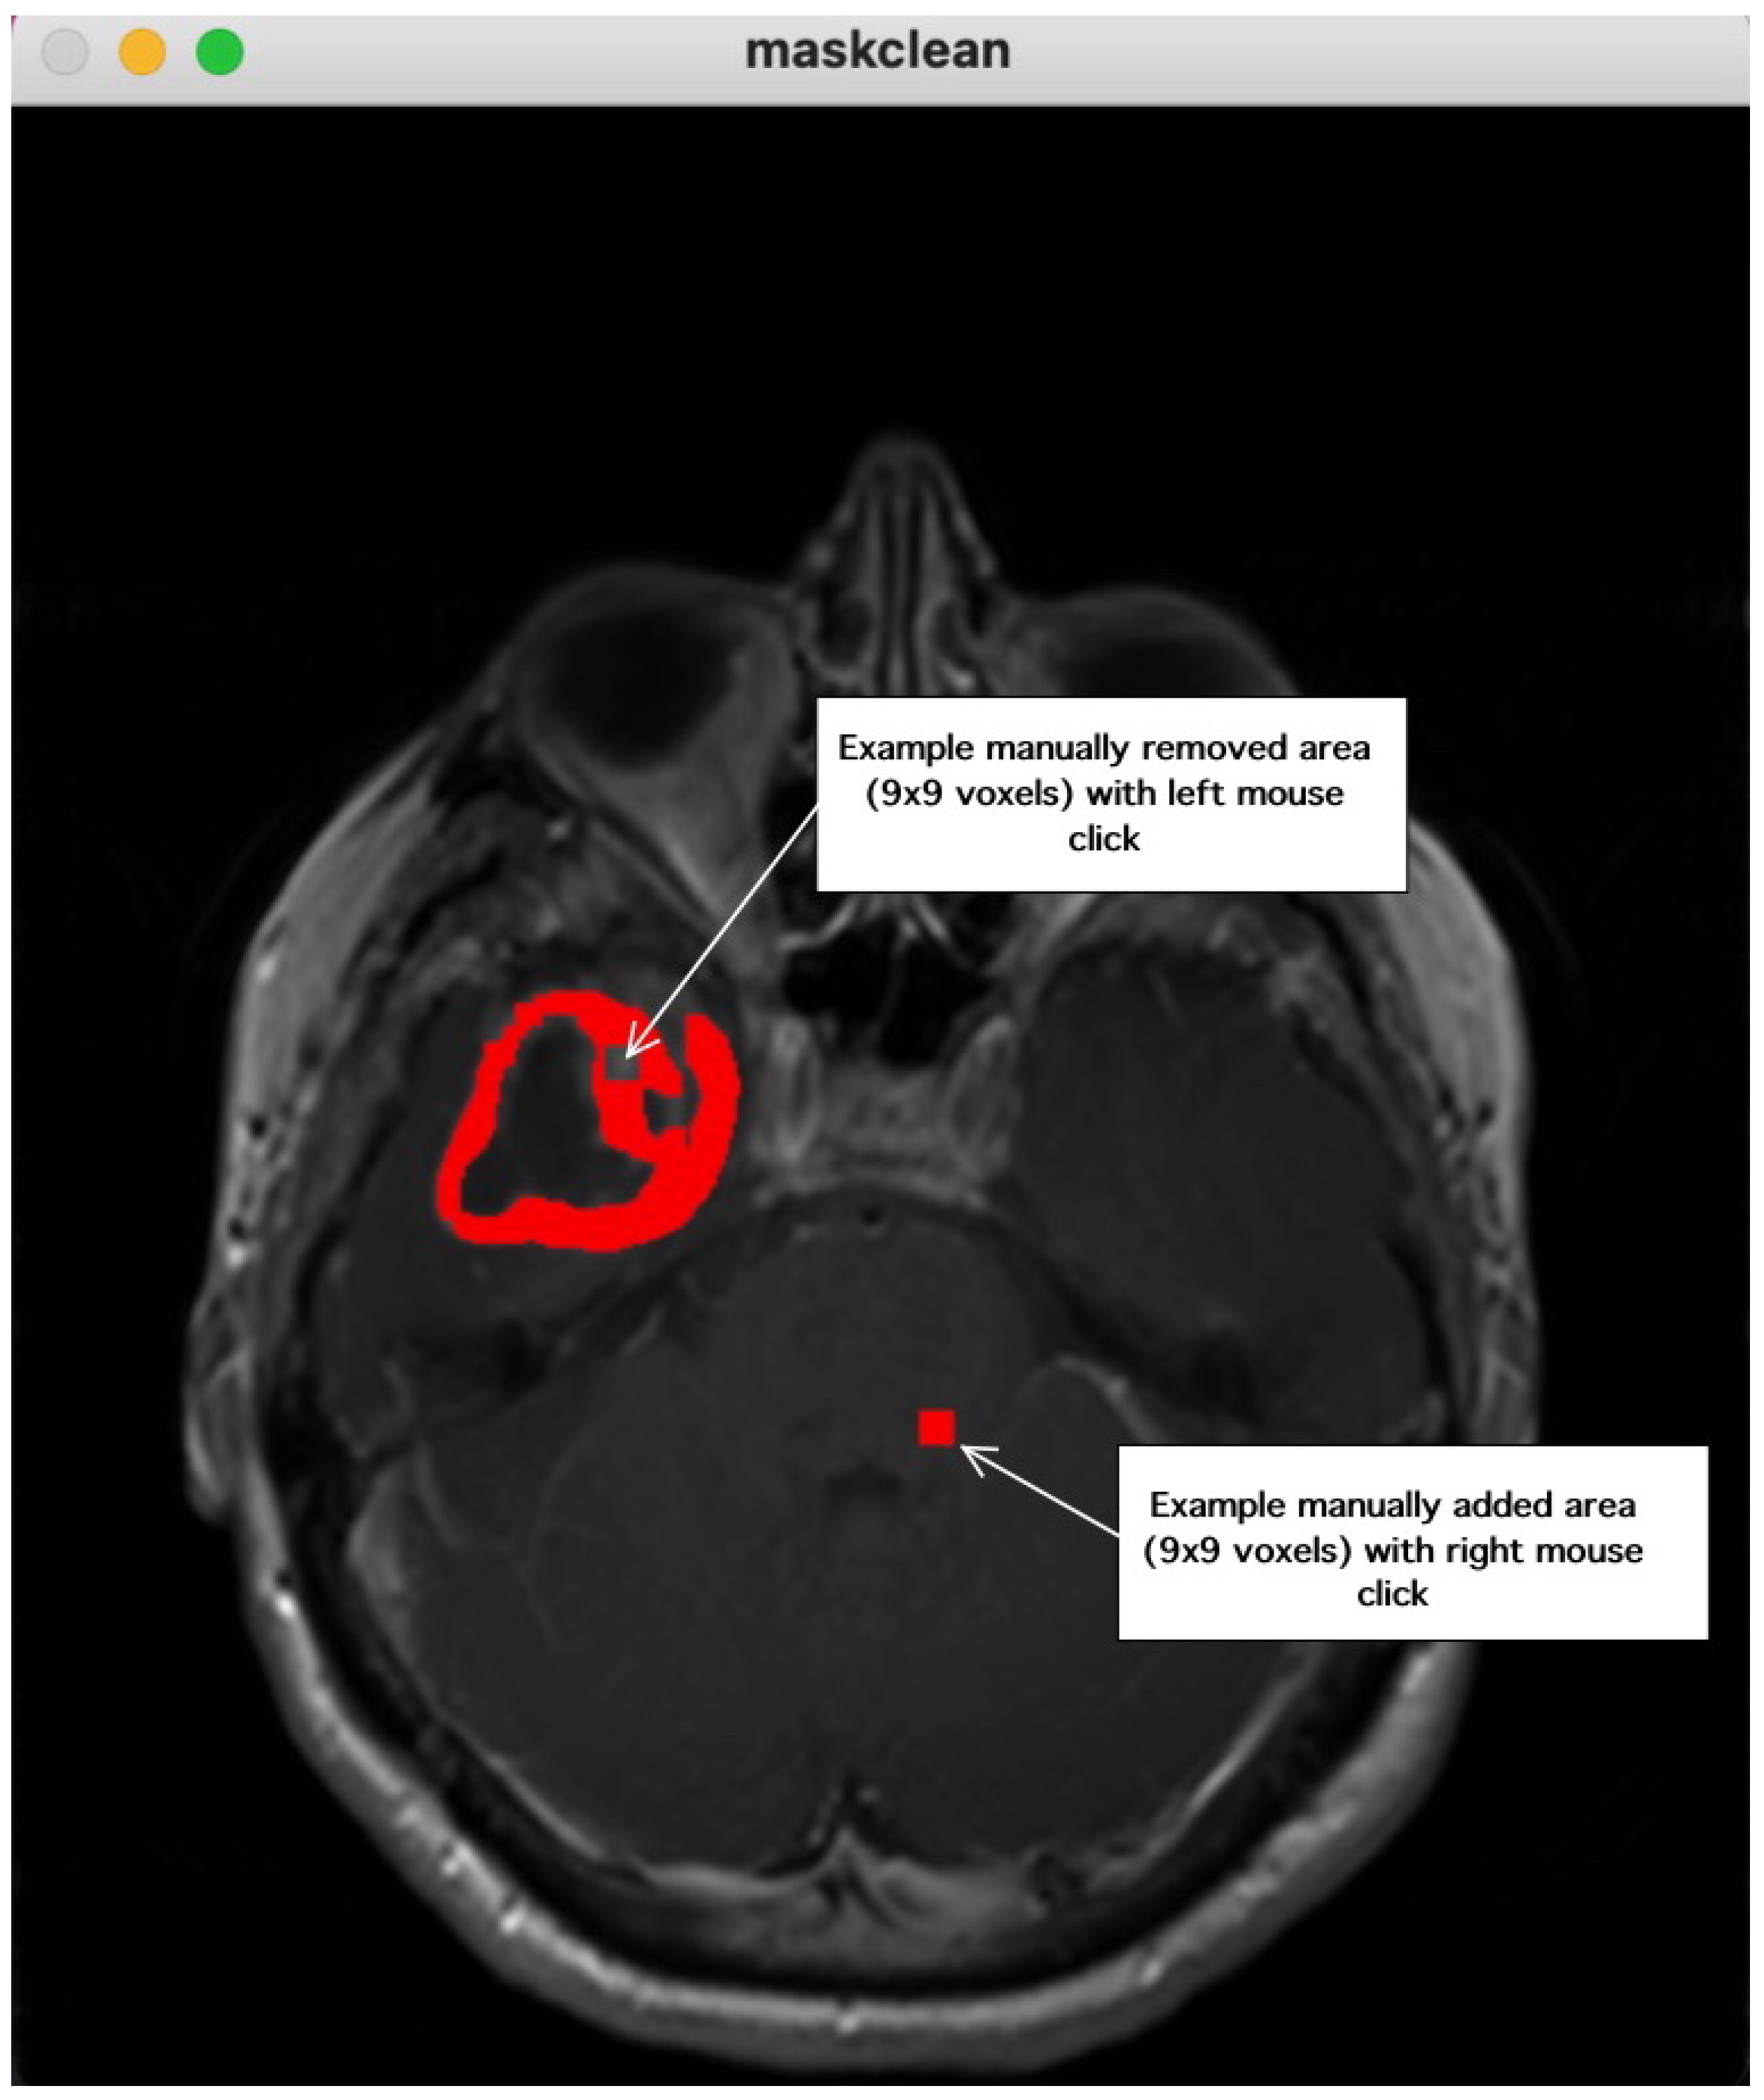

2. Method Description